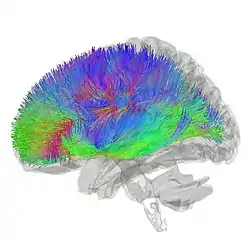

![]() Tractography showing corticostriatal connections | |

[30] The largest connection is from the cortex, in terms of cell axons. Many parts of the neocortex innervate the dorsal striatum. The cortical pyramidal neurons projecting to the striatum are located in layers II-VI, with the most dense projections come from layer V.[31] They end mainly on the dendritic spines of the spiny neurons. They are glutamatergic, exciting striatal neurons.

The striatum is seen as having its own internal microcircuitry.[32] The ventral striatum receives direct input from multiple regions in the cerebral cortex and limbic structures such as the amygdala, thalamus, and hippocampus, as well as the entorhinal cortex and the inferior temporal gyrus.[33] Its primary input is to the basal ganglia system. Additionally, the mesolimbic pathway projects from the ventral tegmental area to the nucleus accumbens of the ventral striatum.[34]

Another well-known afferent is the nigrostriatal connection arising from the neurons of the substantia nigra pars compacta. While cortical axons synapse mainly on spine heads of spiny neurons, nigral axons synapse mainly on spine shafts. In primates, the thalamostriatal afferent comes from the central median-parafascicular complex of the thalamus (see primate basal ganglia system). This afferent is glutamatergic. The participation of truly intralaminar neurons is much more limited. The striatum also receives afferents from other elements of the basal ganglia such as the subthalamic nucleus (glutamatergic) or the external globus pallidus (GABAergic).